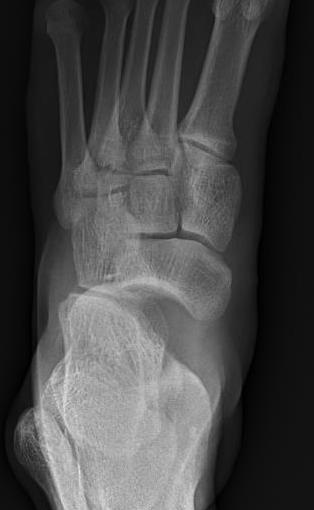

Chopart joints

- talonavicular joint

- calcaneocuboid joint

Ligamentous +/- fracture dislocations

Fractures - trans-navicular / trans-cuboid